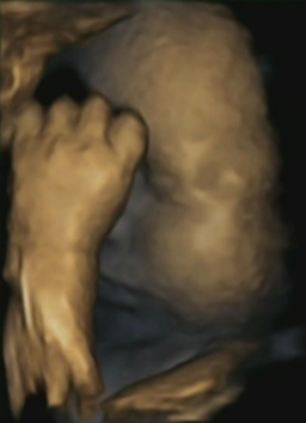

Cand bebelusul isi duce mana la gura si, eventual, se trage de obraz, pare ca este stresat. Aceasta imagine uluitoare a fost facuta in cadrul unui studiu care incearca sa demonstreze ca bebelusii nenascuti isi ating chipul mult mai des daca mamele lor sunt anxioase, lipsite de ajutor, sub presiune.

Cercetatorii cred ca bebelusii preiau nelinistile mamelor si apoi incearca sa le indeparteze prin puterea atingerii, potrivit Daily Mail. Ca adulti, incercam sa facem asta tinandu-ne capul in ambele maini, insa copiii mamelor stresate prefera sa se atinga cu o mana.

Cercetatoarea Nadja Reissland, de la Universitatea din Durham a urmarit 15 femei gravide, carora le-a facut ecografii 4D pe toata perioada sarcinii. Acestor mame li s-a evaluat nivelul de stres si a rezultat ca bebelusii isi atingeau fata atunci cand mamele lor aveau stari de neliniste.